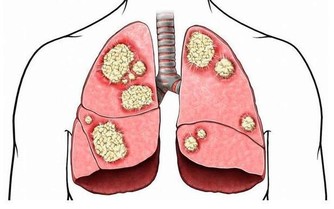

二、肩頸堵塞會引起:

1、影響面部的循環、排毒、呼吸和吸收。

①、用了很久專業護理,但沒有多大效果。

②、面部晦暗、沒有光澤、膚色不均、皮膚鬆弛與實際年齡不符。

③、有倦容、抵抗力差、易過敏、易留色素印、長斑。

2、頭部供血不足。

①、頭痛、頭暈、偏頭痛

②、記憶力減退、健忘

③、睡眠質量差(多夢、易醒、難以入睡)

3、肩頸阻塞。

手按上去後就會有痛,酸漲的現象(肌肉硬是勞損,骨頭痛是增生)肩胛骨縫痛、

經常四肢發麻,手腳冰涼 做事韌性差,易在短時間出現疲勞現象。

4、激素分泌失調。

腦下垂體生長動情激素、內分泌失調、心理神經敏感、易怒、不自信、多疑,頸椎變形,

會造成腰椎變形,腰椎變形會壓迫坐骨神經,坐骨神經會壓迫附盆腔,

同時引發內分泌失調:腰酸背痛,腿腳無力,易疲勞,內分泌失調,月經不調,痛經,易肥胖,婦科感染,性生活失調,宮頸糜爛,子宮肌瘤等等。

五、肩頸堵塞會有哪些症狀呢?

毒素堆積在肩頸以後就會壓迫血管,使血液無法很好的輸送到頭部和麵部,

就會引起頭部的頭暈、頭痛、大腦供氧不足,易疲勞、睡眠質量下降、記憶力減退,

還會引起面部發黃、發暗、長斑、皮膚衰老等。